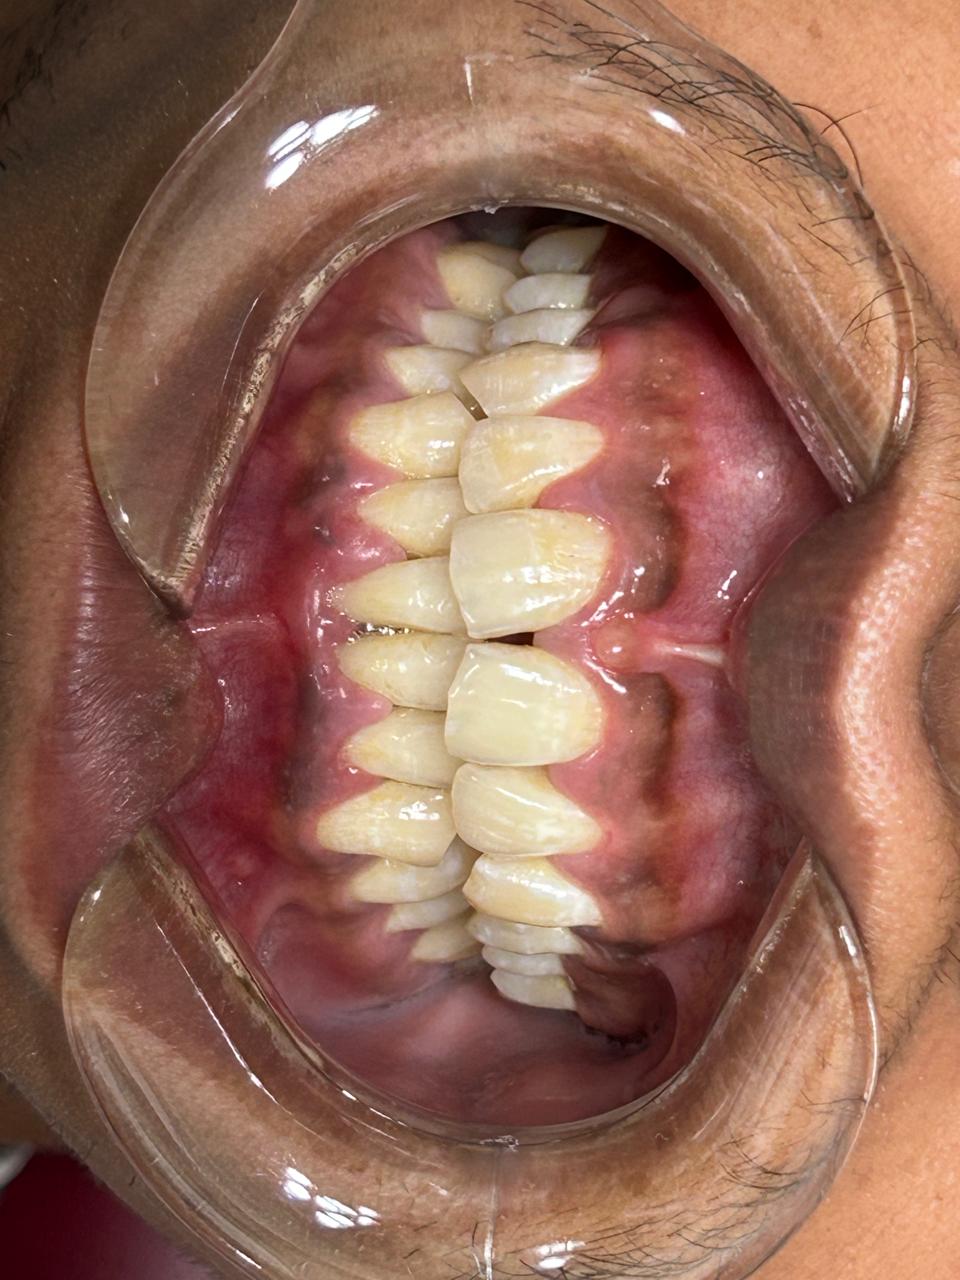

Aesthetic Dentistry

Aesthetic dentistry enhances smile appearance through customized treatments that improve tooth shape, colour, alignment, and overall facial harmony.

Full Mouth Rehabilitation

Comprehensive treatment that restores function, comfort, and aesthetics by addressing multiple dental issues through a personalized, phased approach.